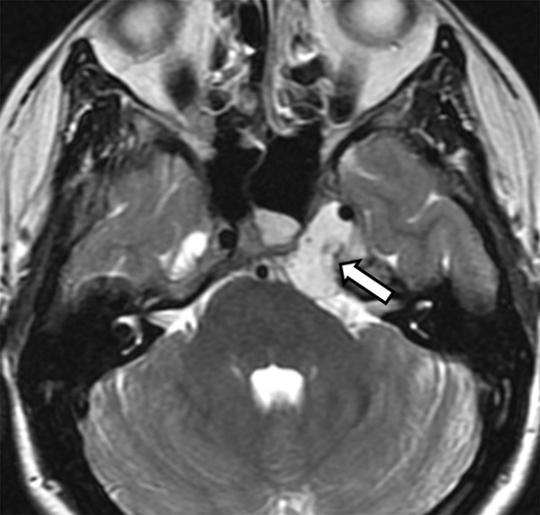

Corte axial de resonancia magnética (RM) en imágenes ponderadas en T2. Paciente que consultó por sensación de oído derecho tapado e hipoacusia. Se observó una lesión que ocupaba y obstruía la fosa de Rosenmüller derecha (flecha) asociada a otitis serosa homolateral (cabeza de flecha). La lesión correspondió a un carcinoma escamoso de nasofaringe.